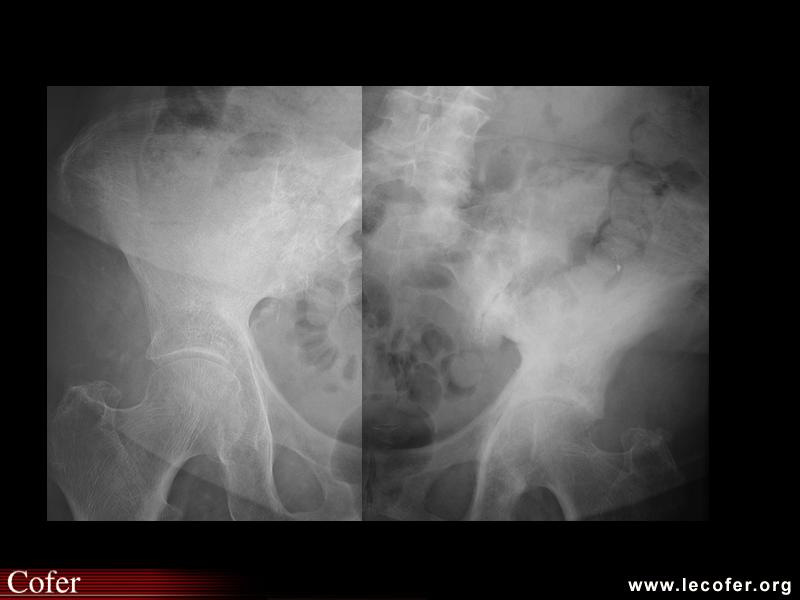

Ostéonécrose aseptique des deux têtes fémorales